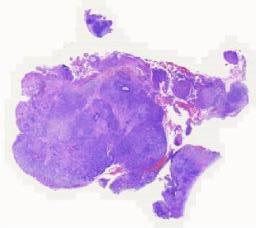

大体所见: 灰白、灰褐破碎组织一堆,切面灰白、灰褐质软,总大小4.5x4.5x2.7cm。